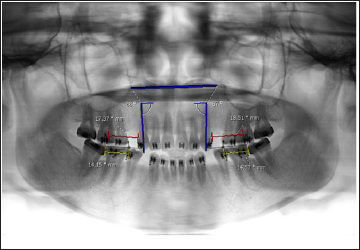

At the first Orthodontic record and treatment plan, participants had x-ray panoramic, lateral cephalometric and full mouth parallel radiographs taken. During research, digital panoramic radiographs was recorded 3 times. First time, at the start of canine retraction and then every 9 weeks later. Calibrated measuring wires of 15 mm. in length were ligated to brackets on both sides prior to radiographs taken. These calibrated measuring wires would be used to adjust for magnification distortion inherent in panoramic films. The rate of canine tooth movement was gathered for 3 intervals; phase 1 (3-12 weeks), phase 2 (12-21 weeks and total time (3-21 weeks). Operator performed blinded assessment of canine tooth movement, not knowing the side of LED nor Placebo. Digital measurements was carried out using the Synapse program (PACSDTMU, version 1.0, Fujifilm, Tokyo). The measurements included

a) Distance between distal aspect of canine bracket to mesial aspect of first molar bracket.

b) Canine tooth axis angulation to palatal plane was measured in order to determine type of canine tooth movement. Calibrated measuring wires was used to adjust for the actual distance of canine movement from digital panoramic radiograph. Rate of canine tooth movement per week was then calculated using the below formula (Figure 3).

Figure 3: Measurement of canine tooth movement and tooth angulation from digital panoramic radiograph using Synapse program.

Actual tooth movement = (X-ray tooth movement x 15 mm)/ X-ray wire length